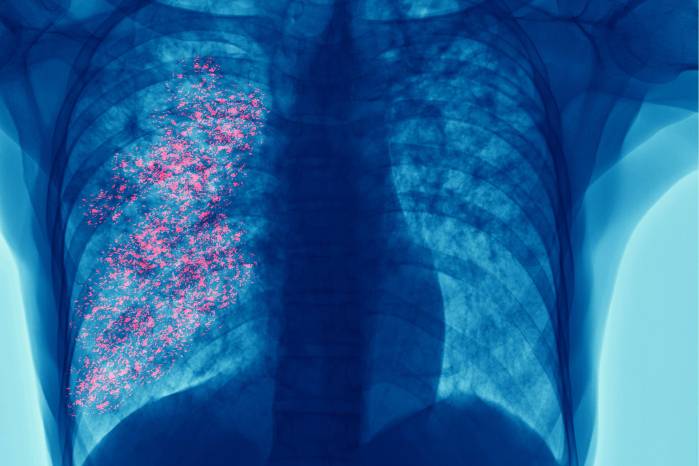

Cada año se reportan 2.4 millones de nuevos casos y 1.8 millones de muertes, lo que representa el 18.7 % de todas las defunciones por cáncer. En Panamá, se registran aproximadamente 370 nuevos casos y más de 300 muertes anuales, lo que ubica al cáncer de pulmón como el cuarto con mayor mortalidad en el país.

El tabaquismo sigue siendo el principal factor de riesgo, responsable del 64 % de los casos y del 79 % de las muertes. A esto se suman la exposición al humo de segunda mano, la contaminación ambiental, el humo de leña y enfermedades respiratorias previas como la EPOC, que aumentan significativamente el riesgo.